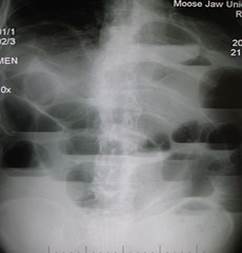

Radiography. Order plain radiographs first for patients in whom SBO is suspected. At least 2 views, supine or flat and upright, are required. Too findings were more predictive of a higher grade or complete SBO: presence of air-fluid differential height in the same small-bowel loop and presence of a mean level width greater than 25 mm. When these findings are present, the obstruction is most likely high grade or complete. When both are absent, a low (partial)-grade SBO is likely or nonexistent. Absent or minimal colonic gas indicates SBO (fig.19).

Figure 19 – Multiple air fluid levels